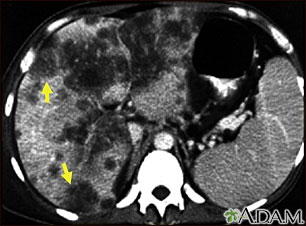

Hepatocellular cancer, CT scan

A CT scan of the upper abdomen showing a widespread (disseminated) carcinoma of the liver (hepato cellular carcinoma). The liver is the large organ on the left side of the picture. Note the moth-eaten appearance.